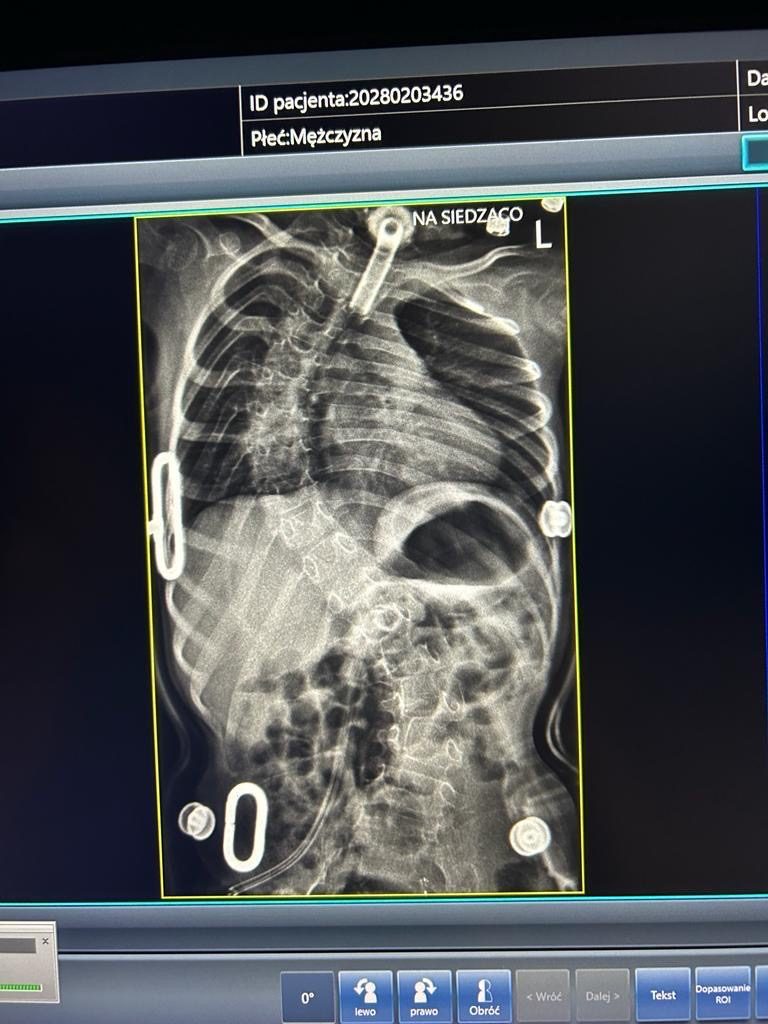

Mam 5 lat i jak każdy mój rówieśnik jestem ciekawy otaczającego świata. Niestety poznawanie go nie jest dla mnie proste. Choruję na bardzo rzadką nieuleczalną chorobę genetyczną SMARD1. Jej nazwa nie jest może straszna ale przez nią nie mogę sam oddychać i moje mięśnie są słabe. Nie potrafię sam usiąść ani chodzić przez co mam okropną skoliozę.

Moi rodzice starają się zastąpić mi nogi a respirator nie działającą przeponę. Mam dużo obowiązków jak na swój wiek. Rehabilitacja to nie tylko moja codzienność, ale i jedyny lek w tym momencie.

Ostatniej zimy ciężko przeszedłem infekcje. Przestałem oddychać, rodzice mnie reanimowali i trafiłem na OIOM. Byłem wprowadzony w śpiączkę farmakologiczną. Lekarze musieli mi wstawić rurkę do oddychania. To już druga bo wcześniej założyli mi jedną do jedzenia. Dzięki temu dzisiaj jestem odżywiony i dotleniony.